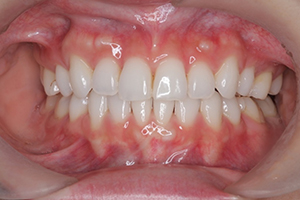

矯正治療のCASE 03

Before

After

- 主訴

- 上下とも歯が出ていて気になる

- 治療内容

- ラビアル矯正(表側)

抜歯あり

- 治療費用

- 88万円~(税込)

- 治療期間

- 18か月

【リスク・副作用】

歯の痛み、口内炎、歯磨きがしにくいことによるむし歯や歯周病のリスク、歯根吸収や歯の変色、後戻りなどの副作用があります。